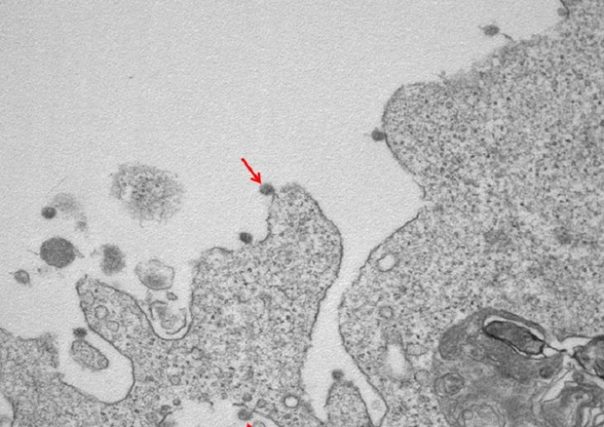

ROMA – Si vede anche la famosa ‘corona’, nel primo ritratto in bianco e nero del virus SarsCoV2 isolato in Lombardia all’Ospedale Sacco di Milano: le immagini al microscopio elettronico mostrano le particelle virali adese alle membrane delle cellule e la loro tipica corona di glicoproteine superficiali. L’annuncio in una nota dell’Università Statale di Milano.

Nella prima, a un ingrandimento di 30000X, si osservano le particelle virali di SarsCov2 (indicate dalle frecce), adese alle membrane sulla superficie e all’interno di cellule utilizzate per l’isolamento.